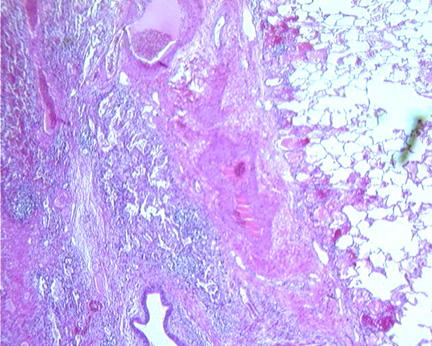

是肺实质坏死形成的亚急性感染。常累及右肺,多于左肺,并且最常见于吸入口咽分泌物之后。肺脓肿表现缓慢,隐匿,通常在初次误吸1-2周后发展。下图显示了肺脓肿。

图1 厚壁肺脓肿

图2 肺脓肿的组织学表现为炎症反应(低倍镜)

图3 肺脓肿的组织学表现为密集的炎症反应(高倍镜)